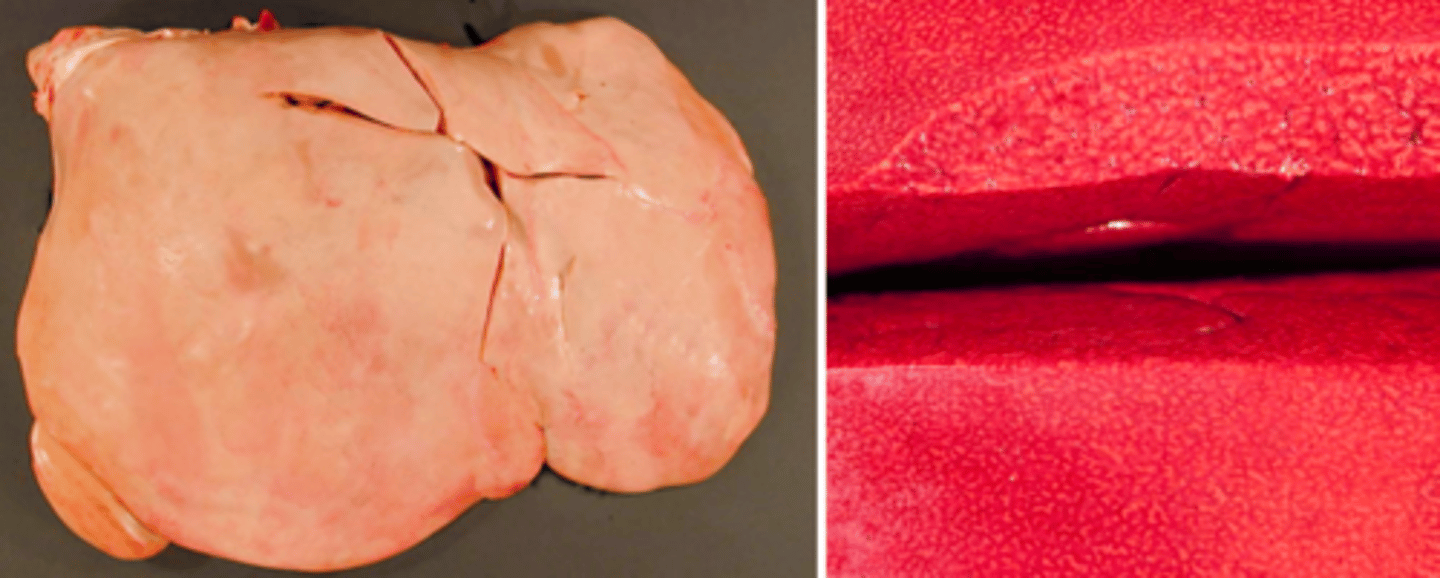

Lever fra svin, hvad er den patoanatomiske diagnose og ætiologien?

Kronisk multifokal, fibrøs, interstitiel hepatitis

Ætiologi: migration af Ascaris suum larver

Lever fra svin, hvad er den patoanatomiske diagnose og ætiologien?

Kronisk multifokal, fibrøs, interstitiel hepatitis

Ætiologi: migration af Ascaris suum larver